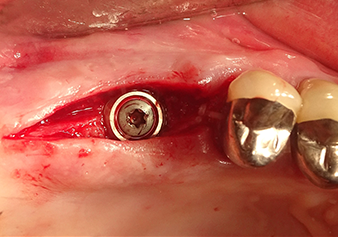

Following atraumatic preparation of the mucoperiosteal flap, the implant position was marked with the I1 instrument and the site prepared – until initial resistance was felt. Piezosurgical instruments were used in an up and down movement without any pressure being exerted. The piezoelectric vibration produced the desired and efficient cavitation.

The I2A instrument (diameter 2.0 mm) was then used to perforate the sinus floor intermittently and on the smallest scale possible. This special piezosurgical method ensures that the Schneiderian membrane is not damaged. When the Z25P was used, the membrane was already lifted slightly by the coolant supplied via the instrument tip (Fig. 3). The coolant quantity was just 50% in order to avoid high pressure in the implant bed.